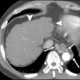

Portopulmonary hypertension (PPH) is defined by the coexistence of portal and pulmonary hypertension. PPH is a serious complication of liver disease, present in 0.25 to 4% of all patients suffering from cirrhosis. [Source: Wikipedia ]

Portal hypertension